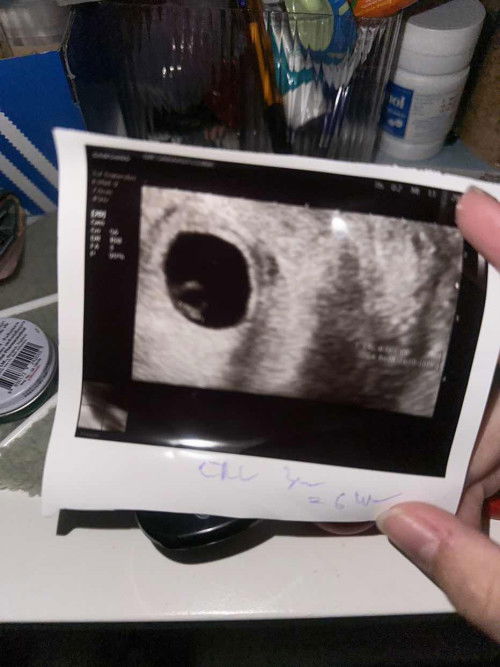

อายุครรถ์จริงกับใบอัลตร้าซาวด์สามารถไม่ตรงกัน

อายุครรถ์จริงกับใบอัลตร้าซาวด์สามารถไม่ตรงกันได้ไหมค่ะ อายุครรภ์ตามกำหนดคลอด15w2d แต่ใบอัลตร้าซาวด์13w

ขนาดตัวอ่อนไม่ถึงเกณฑ์

วันนี้ไปพบหมอ ตามหลักหมอบอกอายุครรภ์6-7w ตัวอ่อนควรจะอยู่ที่2เซน แต่น้องมีขนาดแค่3มิล หมอเลยนัดตรวจใหม่อีก2สัปดาห์ แบบนี้น่ากังวลไหมคะ